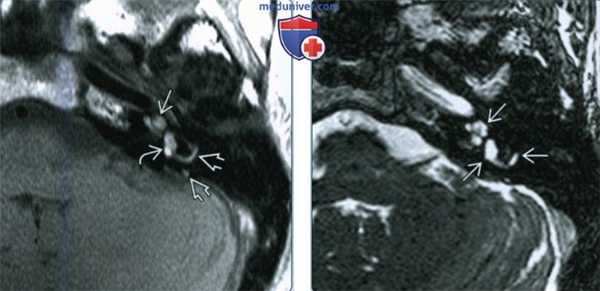

(Слева) При аксиальной МРТ Т1 ВИ без контрастного усиления определяются классические признаки интралабиринтного кровоизлияния (ИЛК): кровь с гиперинтенсивным сигналом (метгемоглобин) в перепончатом лабиринте улитки, преддверии и полукружных каналах.

(Справа) При аксиальной МРТ Т2 ВИ у этого же пациента определяется гиперинтенсивный Т2 сигнал во внутреннем ухе. Сигнал в ИЛК на Т2 ВИ варьирует в зависимости от возраста крови. При снижении интенсивности сигнала диффузное поражение лабиринта помогает отличить ИЛК от интралабиринтных опухолей.